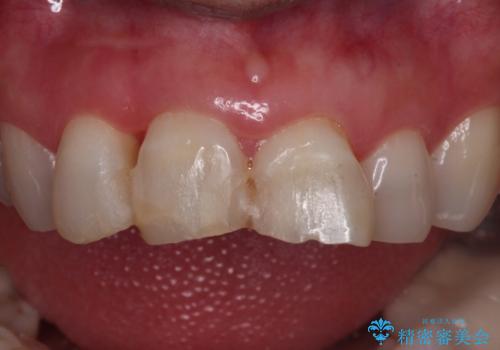

- 転んで前歯が折れたとのことで来院されました。

検査の結果、歯は大きく折れておらず、骨の中に埋め込まれていた状態であったため、部分矯正で歯を引っ張り出していきます。

ぶつけて埋まってしまった歯は、場合によって矯正治療で引っ張り出すことで保存することができます。

今回は歯の神経が死んでしまっていたため、根管治療後に被せ物を装着して見た目の綺麗さを回復しました。